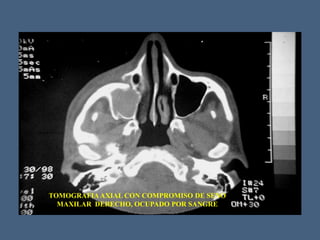

TOMOGRAFIAAXIAL CON COMPROMISO DE SENO

MAXILAR DERECHO, OCUPADO POR SANGRE

TOMOGRAFIAAXIAL CON COMPROMISODE SENO MAXILAR DERECHO, OCUPADO POR SANGRE